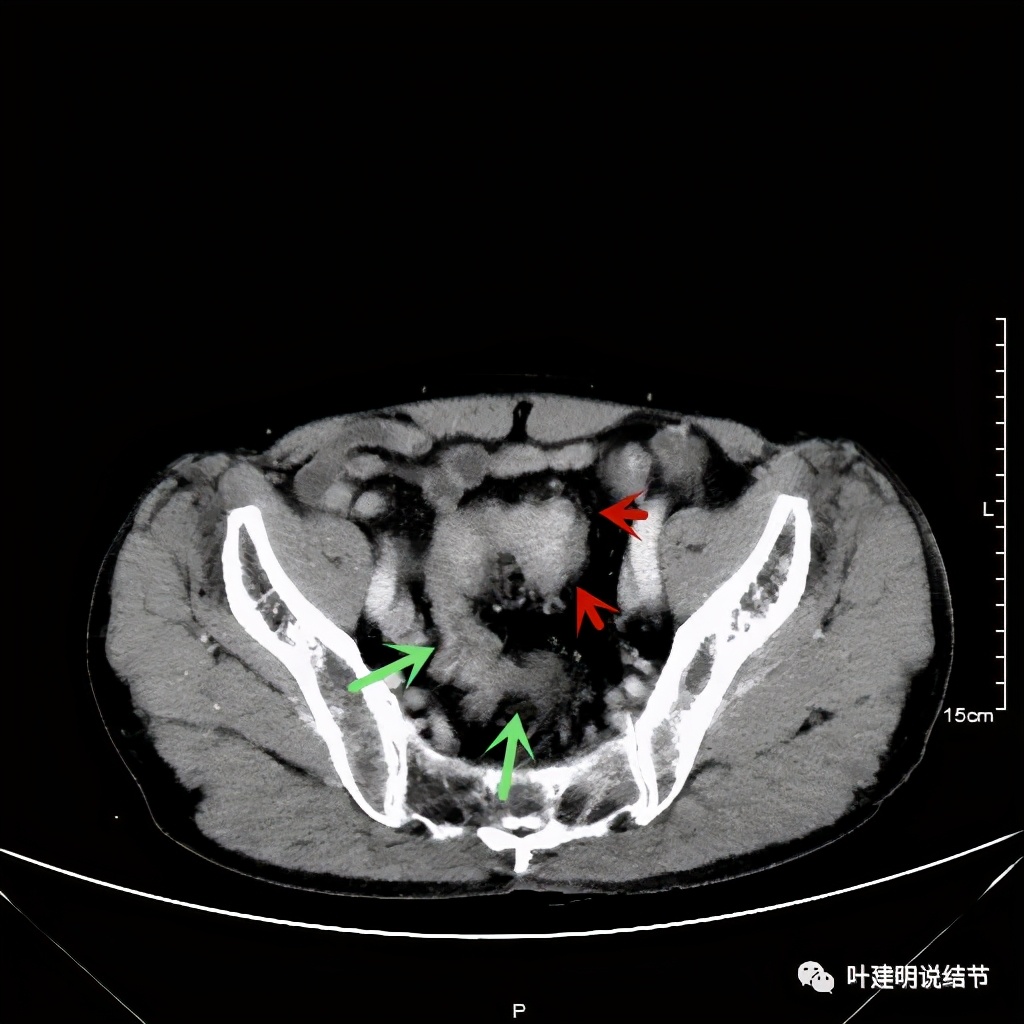

以上诸图红色示乙状结肠肿瘤,绿色示其下方正常的乙状结肠及直肠